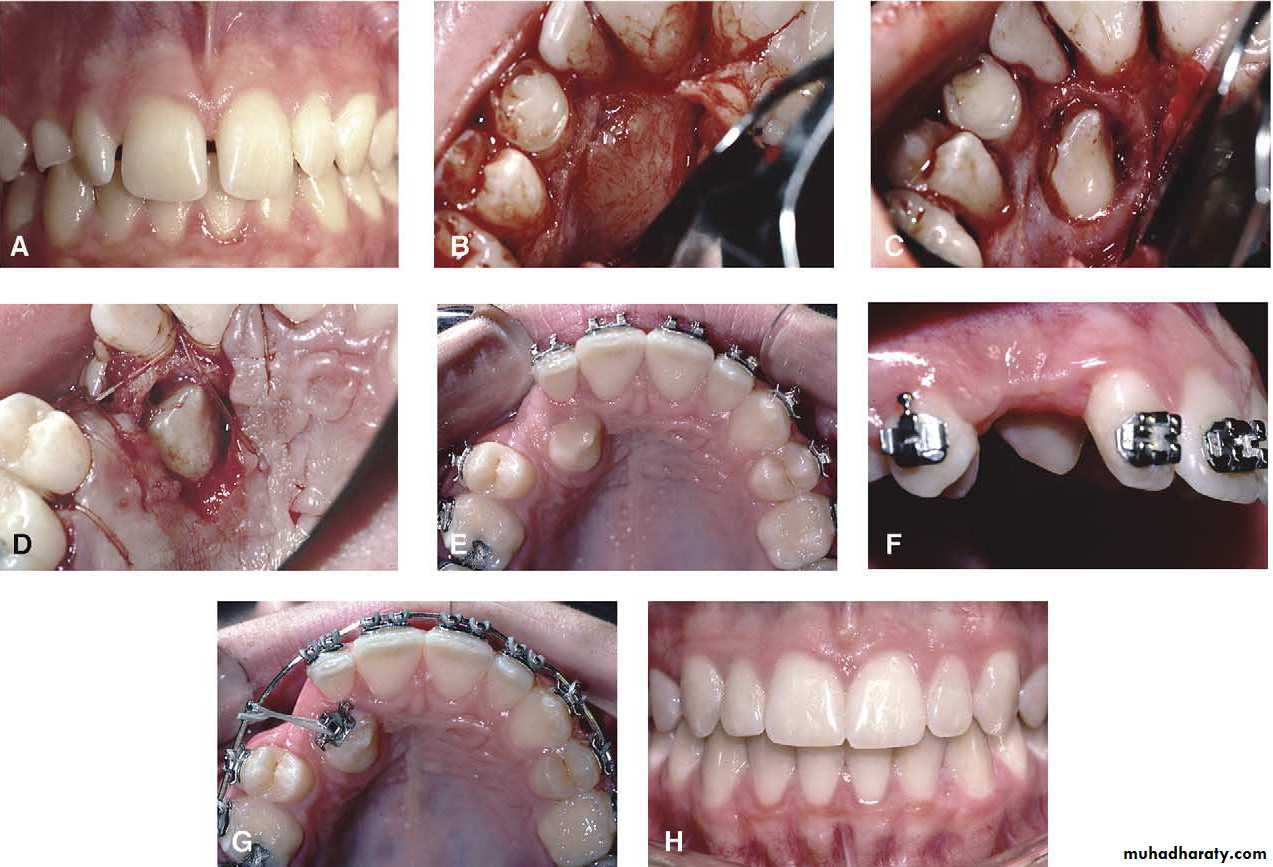

Transplantation and surgical repositioning

The success rate with transplantation is highest for unerupted teeth which have open apices because of the possibility of revascularization .It is essential to establish that there is sufficient space to accommodate the canine crown. minimal space deficiency may be overcome by grinding of the crown , but otherwise orthodontic therapy may be required to move the premolar distally .

Mosul university- College of dentistry-oral & maxillofacial surgery department

The canine should be extracted carefully and transferred to the surgically prepared socket in the dental arch with the minimum of delay.

It is preferable that the root surface should not be touched either with instruments or fingers as the viability of the cementum and periodontal membrane remnants will determine the success of the transplant. The tooth is stored under the flap until the new socket is prepared .

Root filling is not attempted so as to reduce handling of the tooth . The transplanted tooth should be splinted in its new position for a month after the operation .